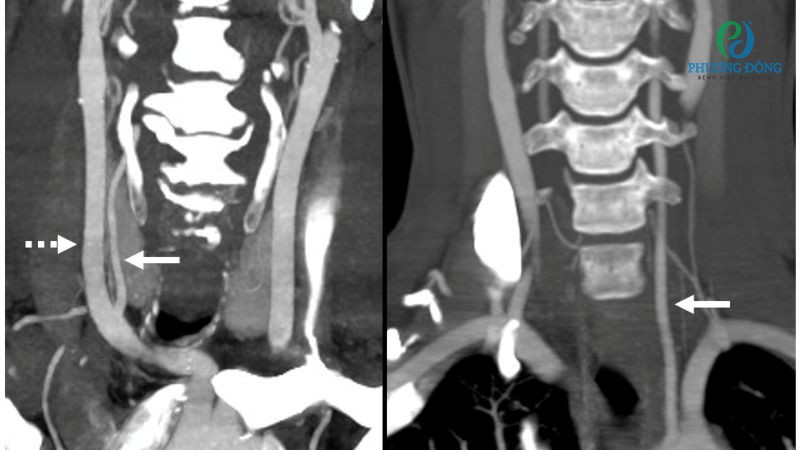

- V3 (đoạn ngoài màng cứng) uốn cong quanh phần trên đốt sống C1 rồi đi vào hộp sọ.

- Tách thành động mạch cổ xảy ra khi lớp trong của thành động mạch bị rách do chấn thương hoặc thành mạch yếu.